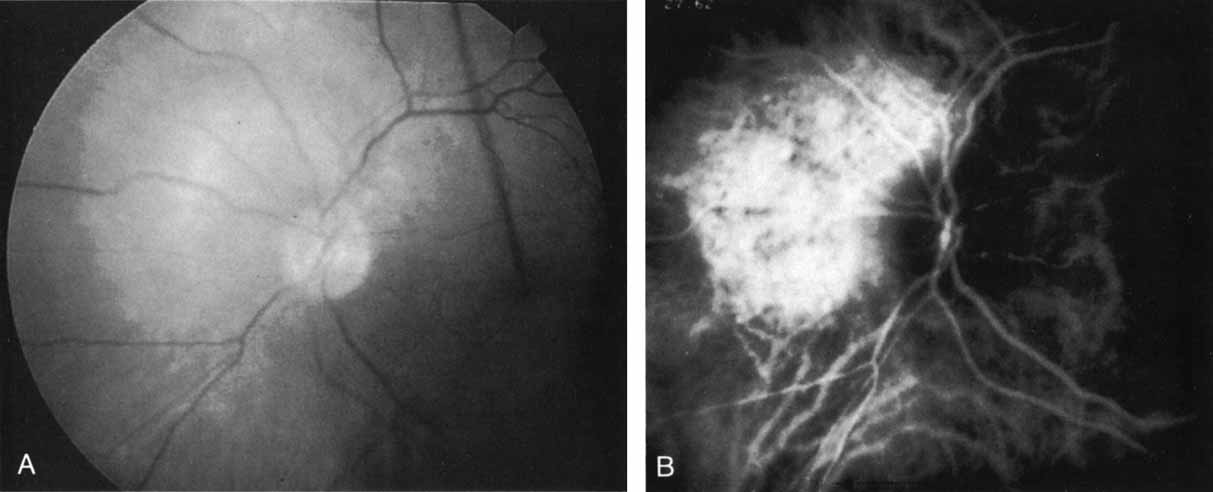

BIRDSHOT CHORIORETINOPATHY

In birdshot chorioretinopathy, the typical clinical appearance of ovoid, cream-colored lesions deep in the retina is easily recognizable on examination. Fluorescein angiography frequently lends very little new information, with minimal irregular hypofluorescence because of blockage of the pigment epithelium. With ICG angiography, the uniform background choroidal fluorescence permits the lesions to stand out in high relief. They appear as ovoid, well-demarcated areas of hypofluorescence that appear to be deep in the choroidal layers (Fig. 14). They have a “vasotropic orientation” following along the distribution of the larger choroidal vessels. The dots visualized with ICG are similar in size to, but are more numerous than, those seen clinically.

Fig. 14 A. Mid-phase indocyanine green (ICG) study in a patient with Birdshot choroidopathy. The arrow corresponds to just one of the multiple sites of hypofluorescence caused by the inflammatory lesions in the choroid. B. Late-phase ICG demonstrating multiple hypofluorecent lesions. C. ICG study in the mid-peripheral fundus demonstrating that these hypofluorescent lesions are aligned along the choroidal vessels.